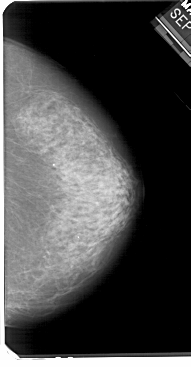

A_1125_1.RIGHT_MLO

RIGHT_CC LINES 5491 PIXELS_PER_LINE 2851 BITS_PER_PIXEL 12 RESOLUTION 43.5 NON_OVERLAY

FILE: A_1125_1.LEFT_CC.OVERLAY

TOTAL_ABNORMALITIES 1

ABNORMALITY 1

LESION_TYPE CALCIFICATION TYPE PLEOMORPHIC DISTRIBUTION SEGMENTAL

ASSESSMENT 4

SUBTLETY 5

PATHOLOGY MALIGNANT

TOTAL_OUTLINES 1

BOUNDARY